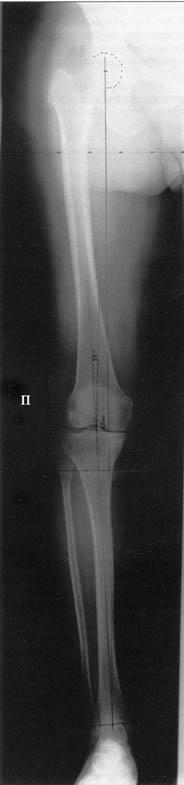

Отправитель: T. Derek V. Cooke 13 Сентябрь 2005, 23:51

|

Hello Alex:

Thanks for the clinical photo.

Your patient appears to have "Insquinting Knees"?

I am attaching a word doc with a 'print screen' of the program in use, showing the images being viewed and analysed

. On the right leg you can see some of the tools (from the tool bar above) applied to demonstrate a mild mech-axis varus of about 5 degrees.

On the left the bone landmarks used in the anlaysis are shown.

The data for the analysis are in the XLs sheet below, exported from the program automatically.

I have given a label of the abreviations and some normative values.

In essence she has a mild mech-axis varus of 7 degrees with some contribution from the femur (2) degrees and more from the tibia (6 degrees), none from the joint.

The analysis took about 6 mins.

Regards

Derek